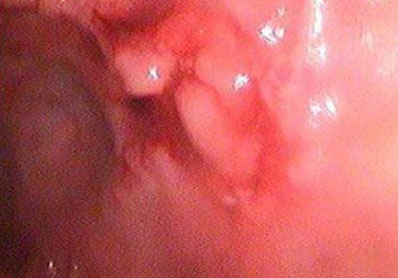

慢性直肠炎是一种发生在直肠内的炎症。慢性直肠炎可以引起疼痛、出血,并会引起直肠流脓和黏液。慢性直肠炎可以维持一段或长或短的时间。当慢性直肠炎的症状扩散到直肠以外,它通常会被认为是直肠外的炎症,因此,慢性直肠炎需要及时治疗。